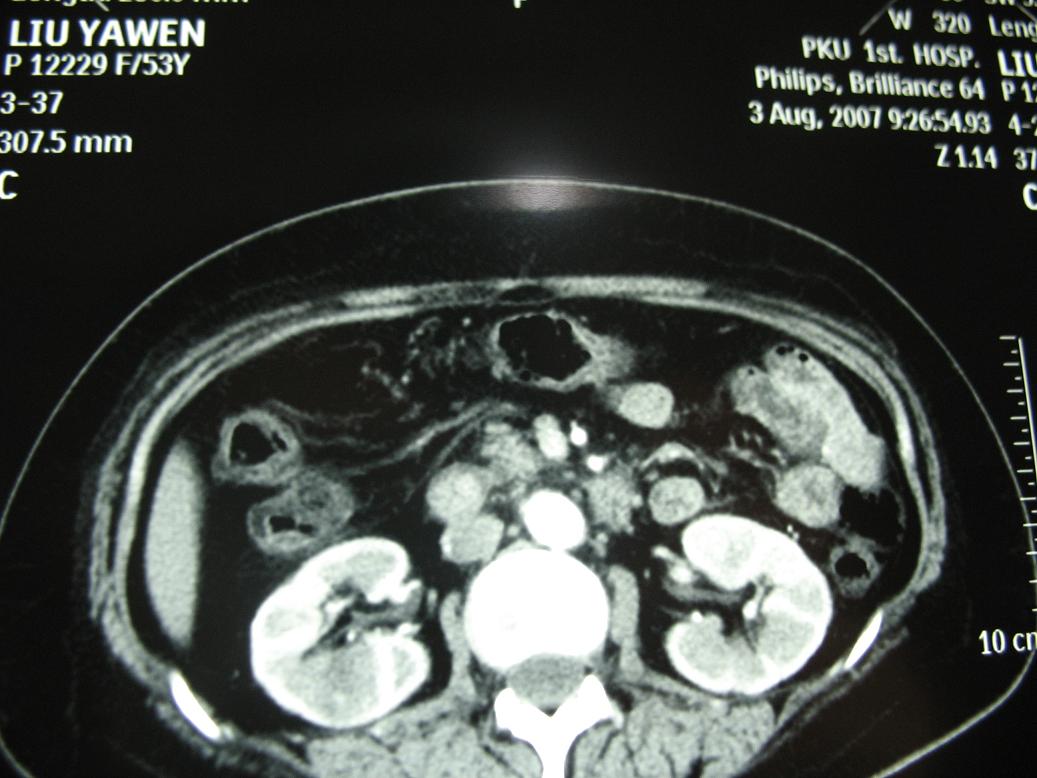

标题: CT17151:女 53岁 腹痛数月余 轻微黄疸 [打印本页]

女 53岁 腹痛数月余 轻微黄疸

1)考虑胰头癌。2)胆囊炎。

壶腹周围占位(钩突ca?)

胰腺钩突mt

支持胰腺钩突ca伴胆系梗阻,胆囊炎

考虑 胰头癌可能性大。